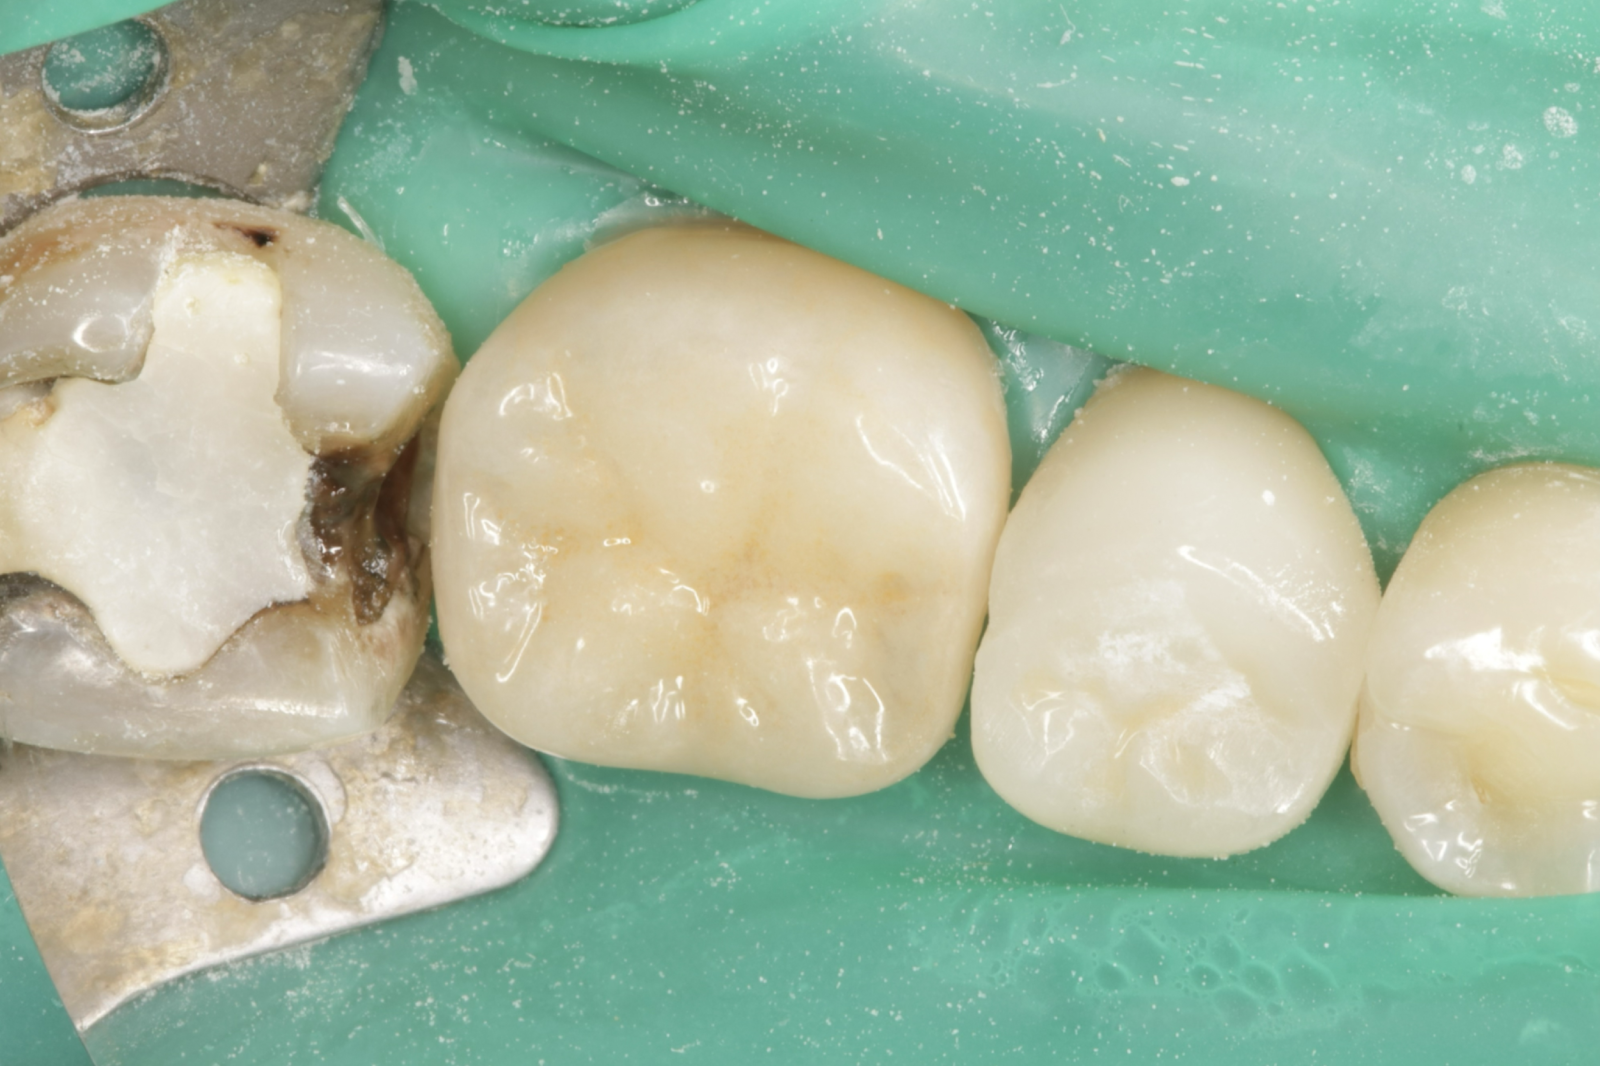

• 治療前

• 治療後